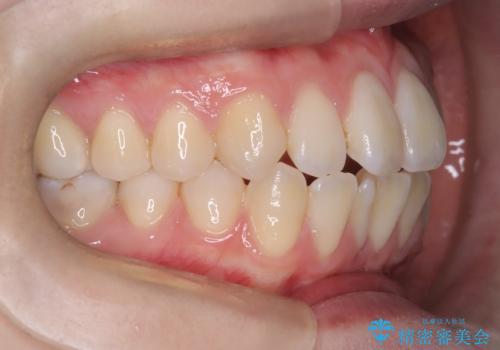

【ワイヤー矯正】前歯の突出感、下の歯の並びを良くしたい

- 主訴:上の前歯の突出感と下の歯の並びを改善したい

非抜歯にて矯正治療を行いました。

IPRを行い、前歯部の突出感の改善に努めました。

期間:1年9カ月